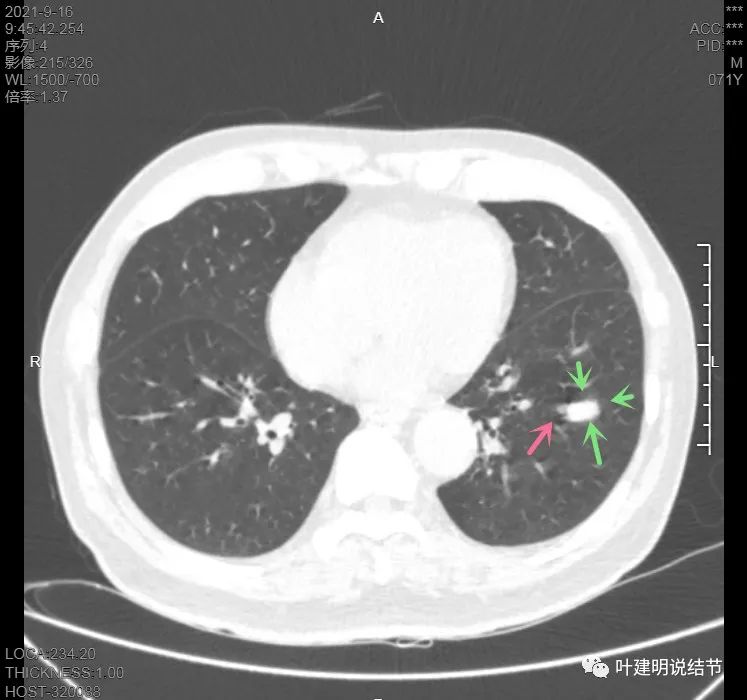

上图见主病灶长方形,边缘平直且光滑,没有毛刺、分叶或胸膜牵拉,粉色箭头示小病灶,在主病灶边上

上图示主病灶边缘非常光滑,膨胀性不明显

上图似乎边缘有点磨玻璃,但这可能是病灶横断面扫到组织相对较少或较薄的地方,其实并不是磨玻璃成分